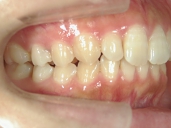

矯正歯科 治療後

矯正歯科 治療後 右